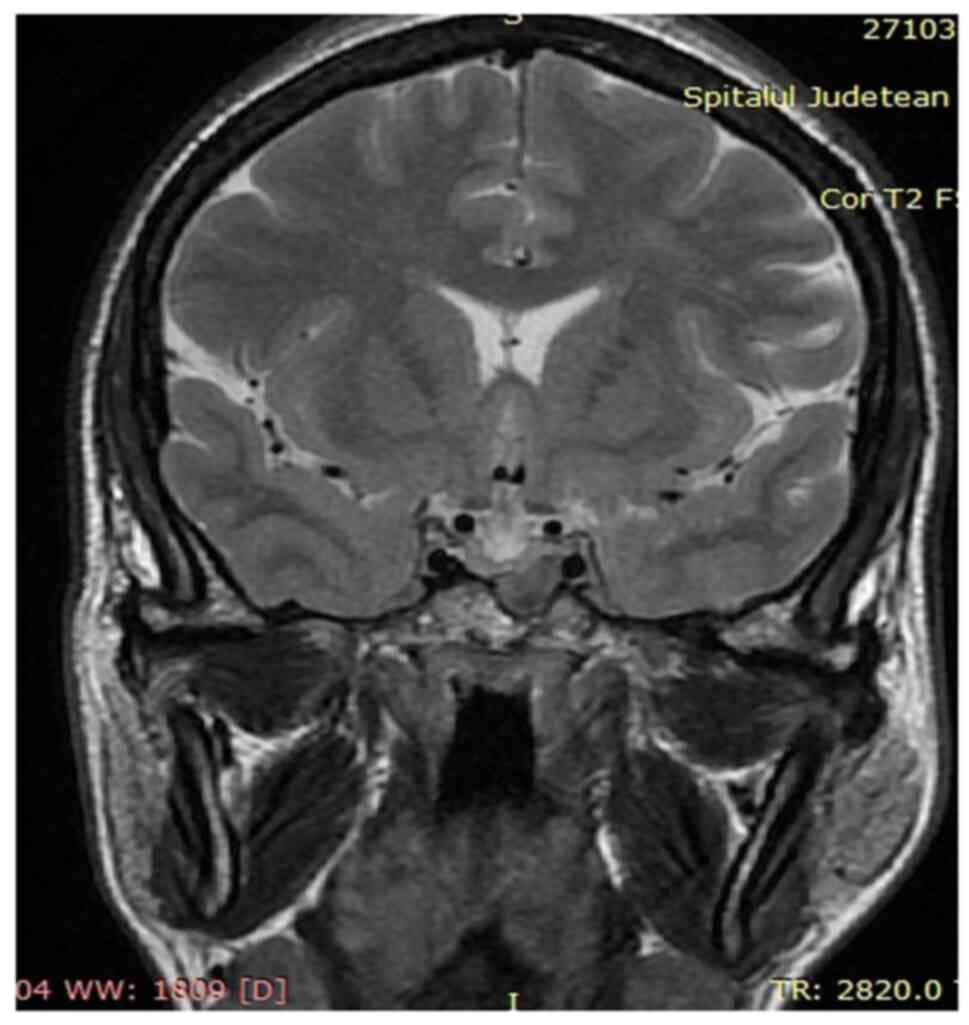

A more detailed history and targeted clinical exam were performed. They revealed the following: Macroglossia, increased interdental spaces (Fig. 4A), enlarged lips, and prominent nasolabial folds (Fig. 4B). The patient also mentioned she was not able to take off her wedding ring for ~5 years. The suspicion of acromegaly was raised and, consequently, IGF-1 (891 ng/ml, normal range for age and sex 83.3-220 ng/ml) and basal GH (20.2 ng/ml, normal value for age and sex <10 ng/ml) were determined. A suppression test with 75 g glucose administered orally was also performed, showing the failure to suppress GH below 1 ng/ml and thus confirming the diagnosis of acromegaly. The evaluation of the global function of the pituitary gland did not identify other hormonal deficiencies (prolactin=4 ng/ml, normal range=2.8-29.2 ng/ml; FSH=75.98 mIU/ml, normal range for menopause=23.0-116.3 mIU/ml; LH=43.05 mIU/ml, normal range for menopause=7.9-53.8 mIU/ml; estradiol <11.80 pg/ml, normal range for menopause <32.2 pg/ml; and cortisol=12.38 mcg/dl, normal range=4.3-22.4 mcg/dl). A pituitary MRI was performed to detect and characterize the adenoma. It revealed a macroadenoma (13/9 mm), hypointense compared to the normal pituitary parenchyma (in T2-weighted signal), which invaded the left sphenoid sinus, without imprinting the optic chiasm (Fig. 5).

Figure 5

MRI, coronal view, T2, hypointense adenoma of 13/9 mm which is invading the left sphenoidal sinus.

Diagnosing and treating the patient, in this case, was a challenge. She did not respond to somatostatin analogues, even though she had predictors for a better evolution, such as being a female of childbearing potential and presenting a hypointense T2-weighted MRI signal of pituitary adenoma (31,32). There are several factors that can influence the response to somatostatin analogues, such as a lack of somatostatin receptors type 2 and 5, Ki-67 nuclear protein, or cytokeratin staining pattern (33). However, they could not be analyzed in the present case.